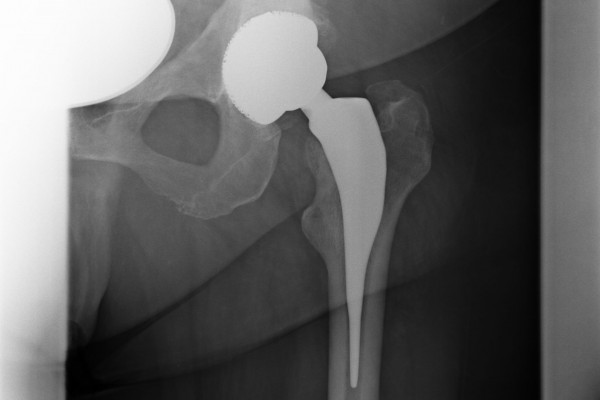

Ziel einer Endoprothese ist es bei der Implantation möglichst viel Knochen zu erhalten. Somit wurden in den letzten Jahrzehnten Prothesenmodelle entwickelt, die aufgrund Ihres Designs eine optimale Krafteinleitung in den Knochen bei maximalen Knochenerhalt gewährleisten. Bei diesen sogenannten Kurzschaftprothesen wird außerdem die Biomechanik des Gelenkes kaum verändert. Dies hat zur Folge dass Sie das Implantat kaum noch bis gar nicht „spüren“.

Anatomische Geradschaftprothese

Um bei etwas schlechteren Knochenverhältnissen eine gute Verankerung zu gewährleisten, kombiniert man in diesem Implantat die Vorzüge der klassischen Geradschaftprothese und der anatomischen Kurzschaftprothese. Das heißt, es wird knochensparend implantiert und aufgrund des längeren Schaftes eine gute Verankerung erreicht. Sollte eine Osteoporose vorliegen, kann dieses Prothesendesign auch zementiert eingebracht werden.